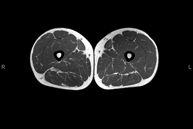

Exploración ideal para el estudio de lesiones en músculos isquiotibiales y cuadriceps, frecuentemente lesionados en deportistas. También permite una buena valoración de tendones y nervios periféricos. Tiene una duración aproximada de 20 minutos. No emplea radiación ionizante. - RM Rodilla